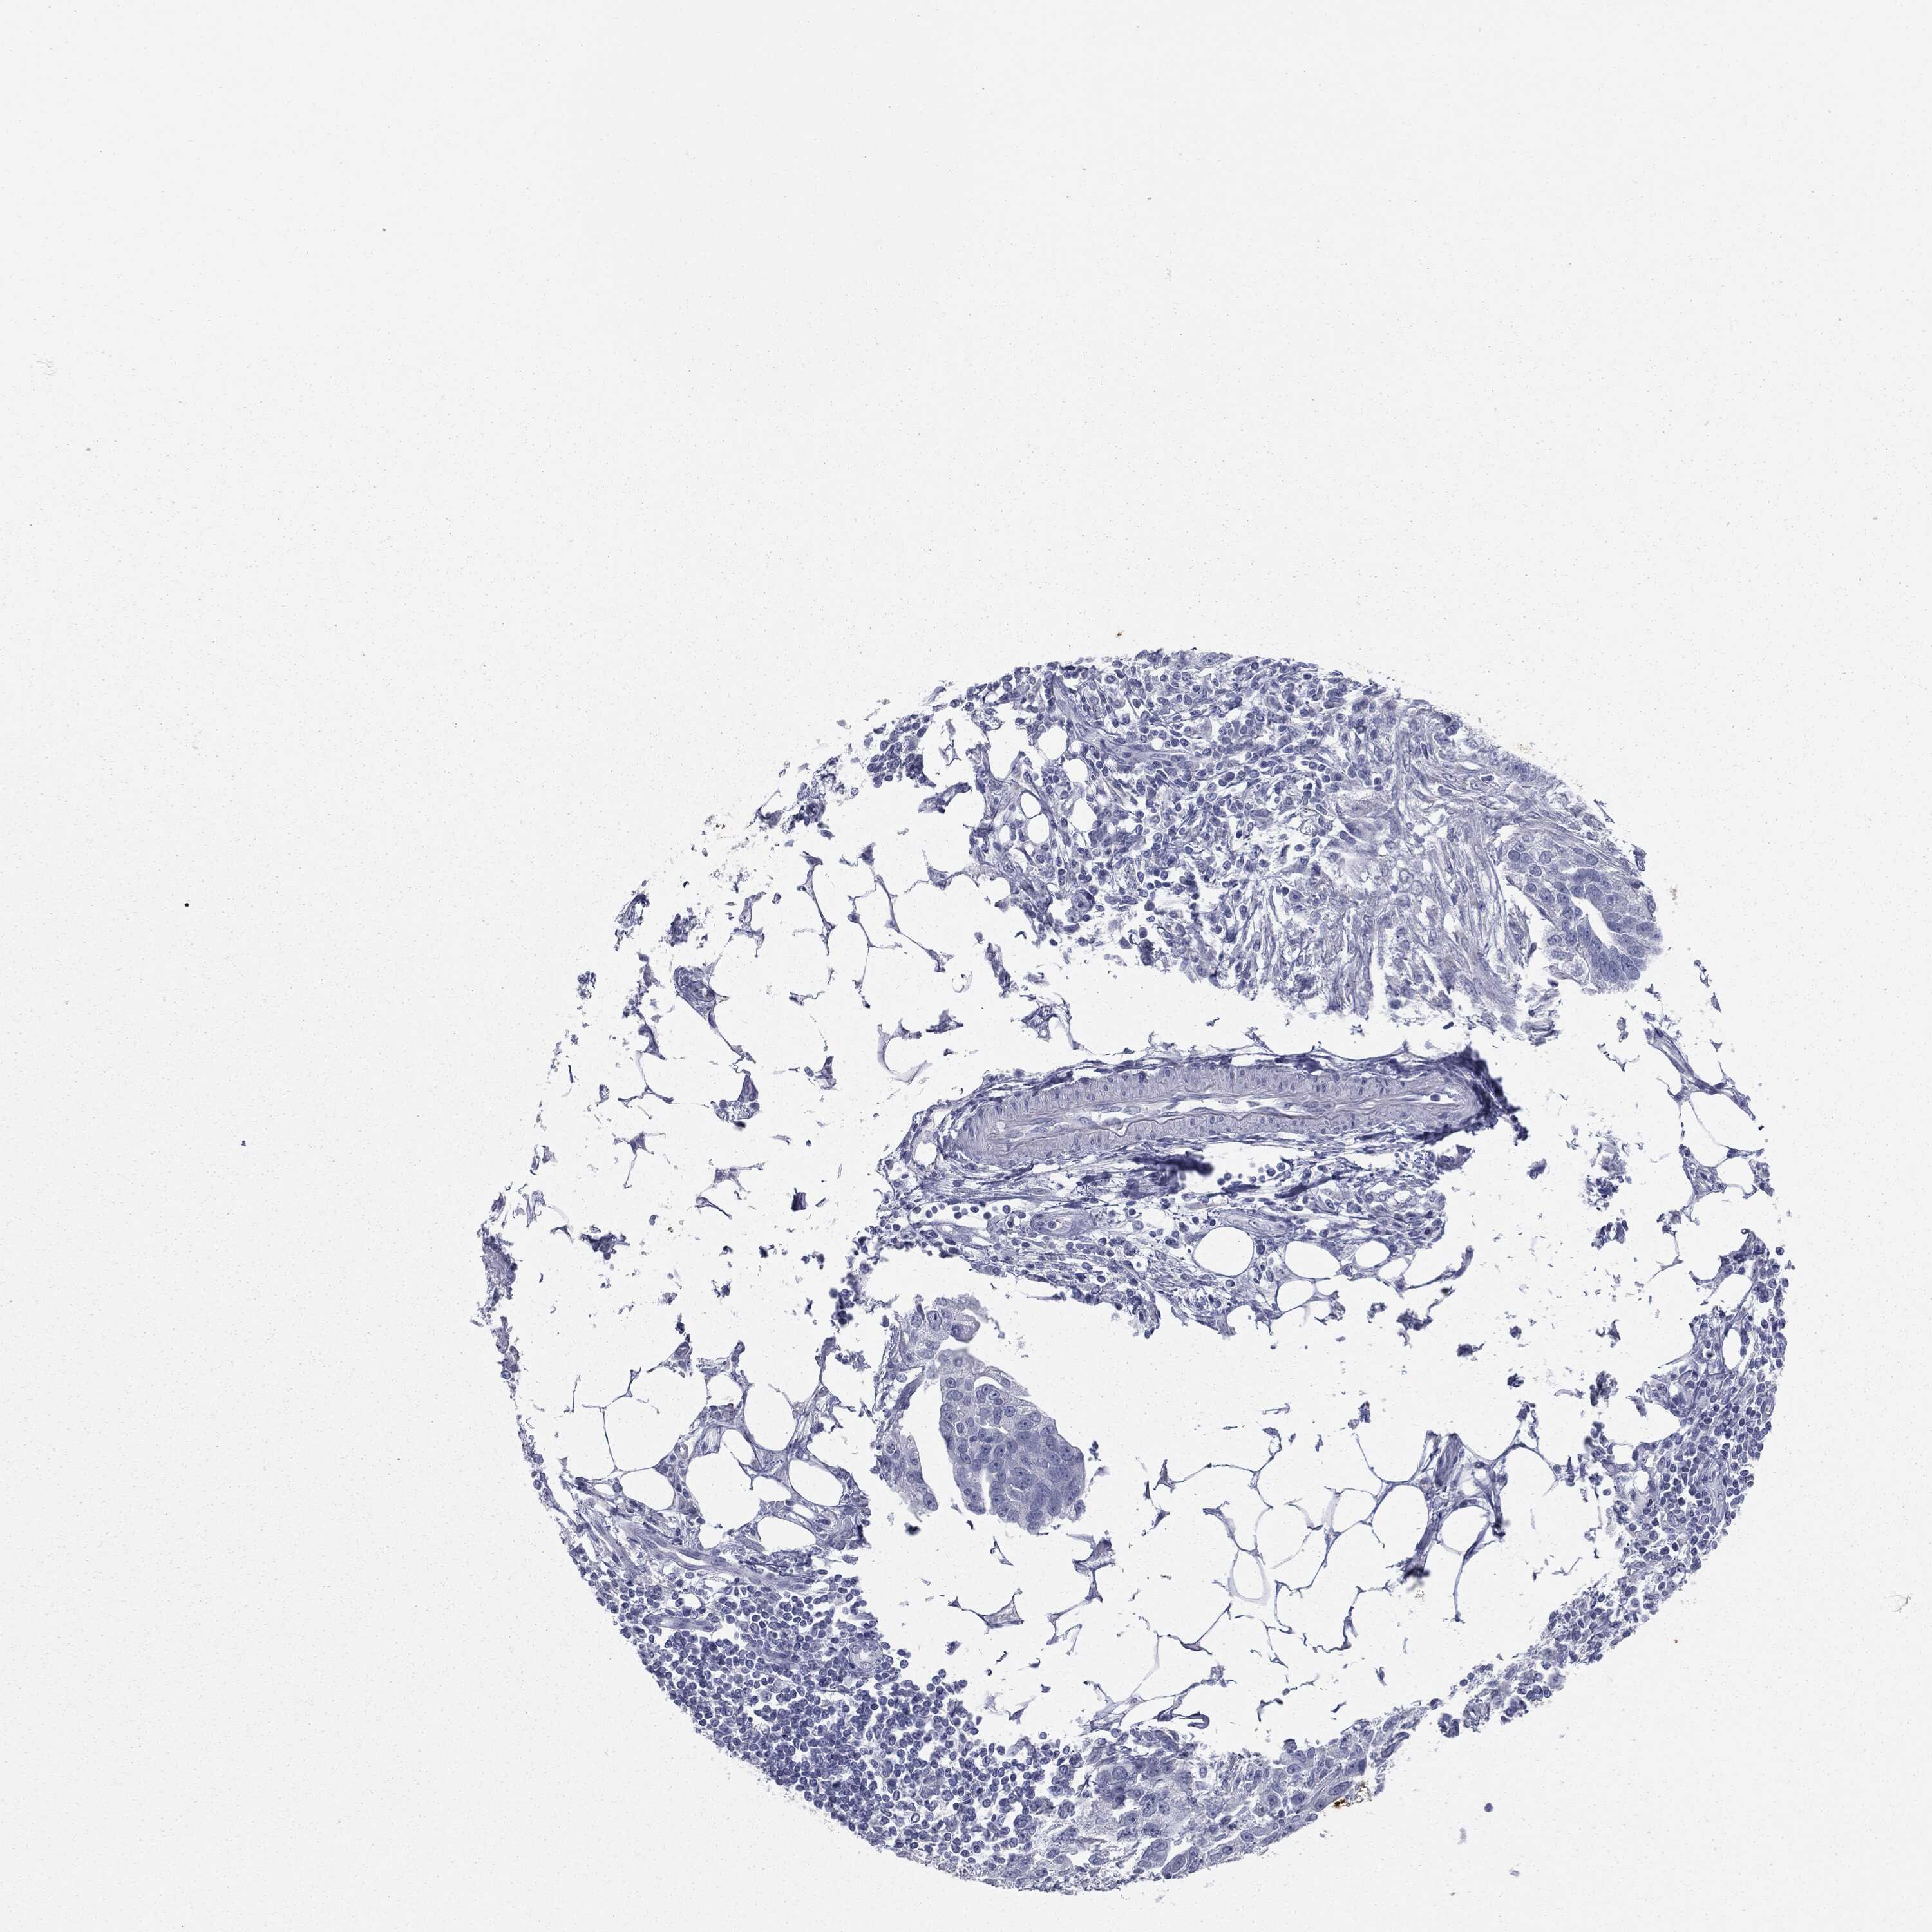

OVARIAN CANCER - Protein expressioni

A mouse-over function shows sample information and annotation data. Click on an image to view it in a full screen mode. Samples can be filtered based on level of antibody staining by selecting one or several of the following categories: high, medium, low and not detected. The assay and annotation is described here.

Note that samples used for immunohistochemistry by the Human Protein Atlas do not correspond to samples in the TCGA dataset.

Antibody stainingi

Antibody staining in the annotated cell types in the current human tissue is reported as not detected, low, medium, or high, based on conventional immunohistochemistry profiling in selected tissues. This score is based on the combination of the staining intensity and fraction of stained cells.

Each image is clickable and will lead to virtual microscopy that enables deeper exploration of all samples and also displays staining intensity scores, fraction scores and subcellular localization as well as patient and tissue information for each sample.

Carcinoma, endometroid